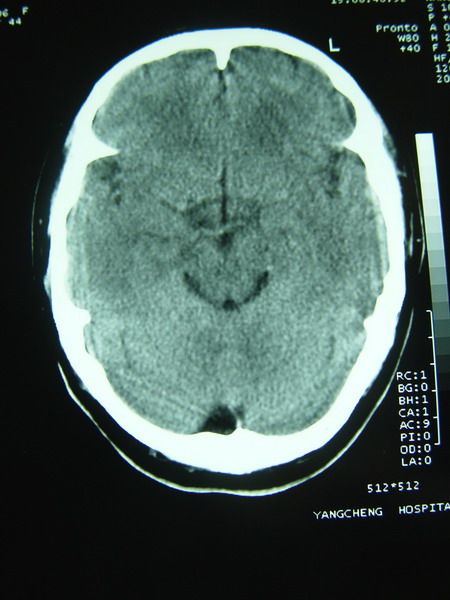

标题: CT12368:女,44岁。突发性左侧肢体麻木4天。 [打印本页]

标题: CT12368:女,44岁。突发性左侧肢体麻木4天。

右侧基底节区腔隙性脑梗塞;右侧顶叶深部及放射冠区病灶考虑机器伪影所致,建议ct增强扫描。

看到黑箭所致的类圆形图形了吧?周围是低密度环形影,用腔隙梗塞来解释很难令人信服。

1确实看到环状低密度影,看症状支持梗塞,最好增强下

2大枕大池?还是脂肪浸润?

枕大池蛛网膜下腔囊肿。右侧半卵圆中心占位性病变,建议强化

应该是机器伪影吧(做一个空气校正或薄层扫描可以改善)。如果是病灶,没有占位效应(排除占位性病变),有4天病史的梗塞灶应该是低密度改变。

右侧半卵圆中心占位性病变,建议强化

但从症状支持脑梗塞诊断,但右侧半卵园中心“影”确实用梗塞及占位都不好解释,可以做一下机器校正后薄层扫描。

枕大池蛛网膜下腔囊肿。右侧半卵圆中心占位性病变。